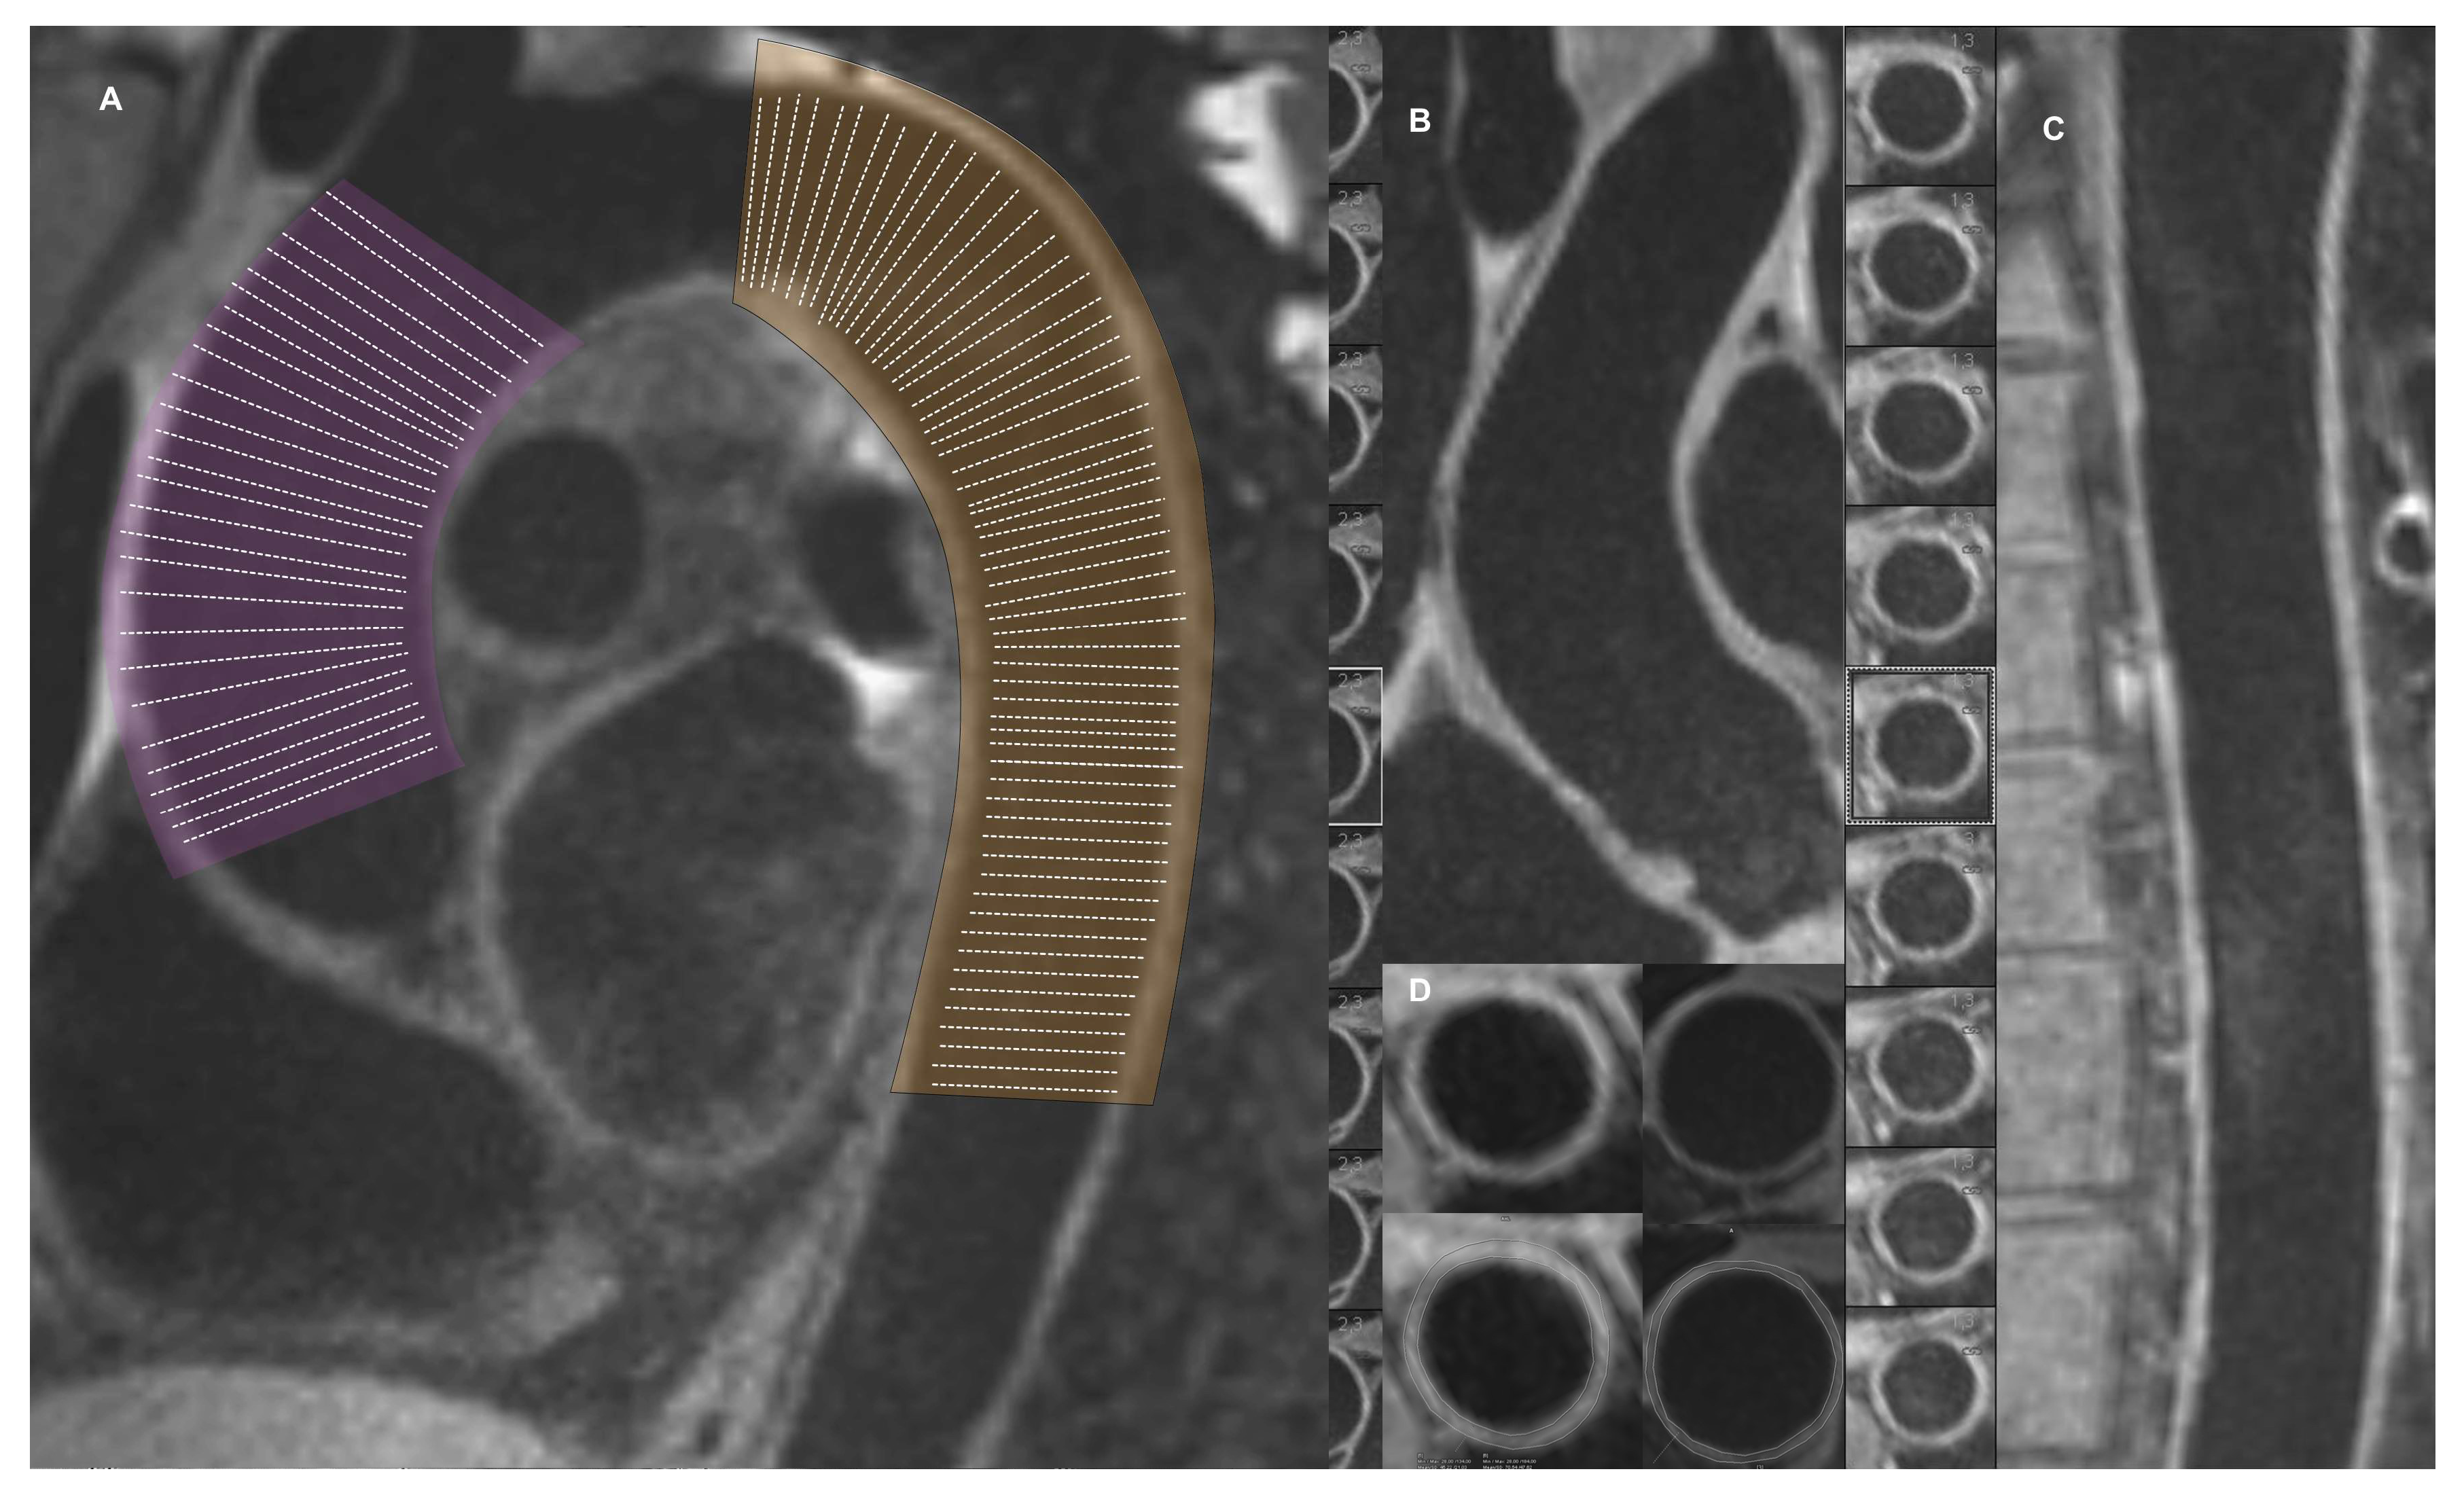

2.2. Cardiovascular Magnetic Resonance